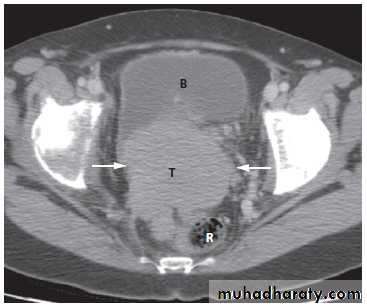

Magnetic resonance imaging is useful to determine the extent of carcinoma of the cervix preoperatively, because the extent (or tumour stage) determines whether the patient is managed with surgery or with chemoradiotherapy.

The observations to be made are whether the tumour is confined to the cervix .

It extends into the parametrium, lymph nodes, rectum, bladder or pelvic side walls .